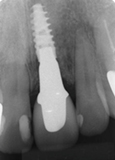

前歯部単独インプラント

治療前

治療後